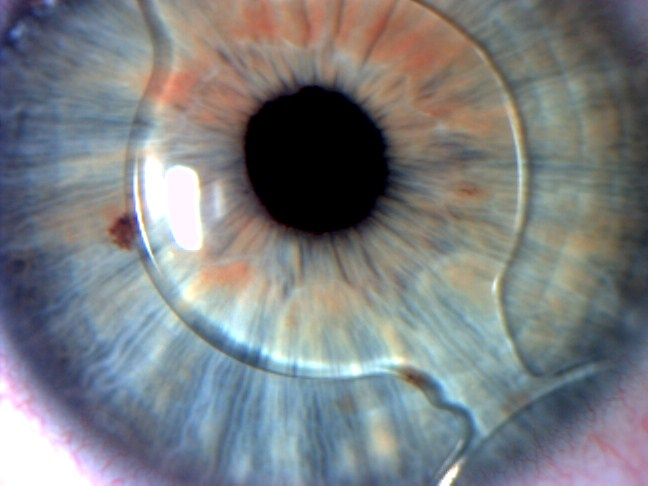

Product id: Lente intraocular on sale faquica

Lentes Intraoculares F quicas introducci n y complicaciones on sale, Iris Fixated Phakic Intraocular Lens Implantation on sale, Implantaci n de lentes intraoculares f quicos y f quicos t ricos on sale, Lentes intraoculares f quicas on sale, Lente intraocular f quico cirug a que permite dejar de usar on sale, Intraocular Lenses Incornea ENG on sale, Visian ICL lentes intraoculares f quicas on sale, Dr. Gonzalo Gallegos La implantaci n de lente intraocular on sale, Implantaci n de lentes intraoculares f quicos y f quicos t ricos on sale, Lentes F quicas oculares rea Oftalmol gica Avanzada on sale, Implante de Lentes Arbrayss L ser Oftalmolog a Pioneros en on sale, Lentes F quicas rea Oftalmol gica Avanzada Dr. Darchuk on sale, Lente Intraocular F quica ICL on sale, Precio Cirugia Intraocular Sale Online SAVE 51 factoria 4 7 on sale, Implante de lentes intraoculares todo lo que debes saber on sale, Correcci n de la alta miop a con implante de lente f quica ACR 128 on sale, Multimedia Dr. Luis Fernando Mej a Oftalm logo Medell n Colombia on sale, Lentes Intraoculares F quicas en Vista Mallorca Facorefractiva on sale, Lentes intraoculares f quicas ICL Cl nicas Tecnovision on sale, Lentes Intraoculares LIO T ricas Cl nica Oftalmol gica Santa on sale, Lente intraocular f quica de c mara anterior de fijaci n angular on sale, Miranza IOA LENTES F QUICAS ICL on sale, Qu son las Lentes F quicas rea Oftalmol gica Avanzada on sale, Lentes ICL o Lentes Intraoculares Ventajas e Indicaciones on sale, Lentes Intraoculares F quicas introducci n y complicaciones on sale, Las lentes intraoculares f quicas una soluci n en auge para on sale, Cirug a de Implante de Lente Intraocular F quico en Ibagu Tolima on sale, Implantaci n de lente intraocular de c mara anterior on sale, Multimedia Dr. Luis Fernando Mej a Oftalm logo Medell n Colombia on sale, Lente Intraocular F quico Curiel Visi n on sale, Lente F quica Dr. Fernando Mayorga on sale, Lente intraocular f quica fotograf as e im genes de alta on sale, Lentes intraoculares f quicas Wikipedia la enciclopedia libre on sale, Vista de Tecnolog as para la emetrop a Archivos Argentinos de on sale, Miop a hipermetrop a y astigmatismo Dr. Diego Croce on sale, Ceoval Centro Oftalmol gico de Valencia Sabes que la lente on sale, Cirug a de lente intraocular Dra. Elisa Nieto Torres on sale, Lentes intraoculares f quicas ICL IO ICO Barcelona on sale, Lente intraocular f quica fotograf as e im genes de alta on sale, Cirug a de catarata explante lente f quica PRL on sale, C mo se coloca el lente intraocular f quico Conoce todos los detalles on sale, Implante de Lente Intraocular Dr Gabriel Oliveros on sale, LENTE INTRAOCULAR Faquico Fijaci n En el Iris ppt descargar on sale, Lentes F quicas Cirurgia para miopia lentes intra oculares on sale, Cirug a de lente f quica Intraocular ICL Smart Laser Eye Center on sale, Dra. Paola Zurita Ferrel Cirujana Oftalm loga Qu son las on sale, Lentes F cicas Altas Ametropias on sale, Lente Faquico Torico en Paciente con Queratocono Operado de Anillos Intraestromales on sale, Cirug as de cambio de color de ojos e implantes de iris on sale, Lente intraocular f quica de c mara anterior de fijaci n angular on sale.

Lentes Intraoculares F quicas introducci n y complicaciones on sale, Iris Fixated Phakic Intraocular Lens Implantation on sale, Implantaci n de lentes intraoculares f quicos y f quicos t ricos on sale, Lentes intraoculares f quicas on sale, Lente intraocular f quico cirug a que permite dejar de usar on sale, Intraocular Lenses Incornea ENG on sale, Visian ICL lentes intraoculares f quicas on sale, Dr. Gonzalo Gallegos La implantaci n de lente intraocular on sale, Implantaci n de lentes intraoculares f quicos y f quicos t ricos on sale, Lentes F quicas oculares rea Oftalmol gica Avanzada on sale, Implante de Lentes Arbrayss L ser Oftalmolog a Pioneros en on sale, Lentes F quicas rea Oftalmol gica Avanzada Dr. Darchuk on sale, Lente Intraocular F quica ICL on sale, Precio Cirugia Intraocular Sale Online SAVE 51 factoria 4 7 on sale, Implante de lentes intraoculares todo lo que debes saber on sale, Correcci n de la alta miop a con implante de lente f quica ACR 128 on sale, Multimedia Dr. Luis Fernando Mej a Oftalm logo Medell n Colombia on sale, Lentes Intraoculares F quicas en Vista Mallorca Facorefractiva on sale, Lentes intraoculares f quicas ICL Cl nicas Tecnovision on sale, Lentes Intraoculares LIO T ricas Cl nica Oftalmol gica Santa on sale, Lente intraocular f quica de c mara anterior de fijaci n angular on sale, Miranza IOA LENTES F QUICAS ICL on sale, Qu son las Lentes F quicas rea Oftalmol gica Avanzada on sale, Lentes ICL o Lentes Intraoculares Ventajas e Indicaciones on sale, Lentes Intraoculares F quicas introducci n y complicaciones on sale, Las lentes intraoculares f quicas una soluci n en auge para on sale, Cirug a de Implante de Lente Intraocular F quico en Ibagu Tolima on sale, Implantaci n de lente intraocular de c mara anterior on sale, Multimedia Dr. Luis Fernando Mej a Oftalm logo Medell n Colombia on sale, Lente Intraocular F quico Curiel Visi n on sale, Lente F quica Dr. Fernando Mayorga on sale, Lente intraocular f quica fotograf as e im genes de alta on sale, Lentes intraoculares f quicas Wikipedia la enciclopedia libre on sale, Vista de Tecnolog as para la emetrop a Archivos Argentinos de on sale, Miop a hipermetrop a y astigmatismo Dr. Diego Croce on sale, Ceoval Centro Oftalmol gico de Valencia Sabes que la lente on sale, Cirug a de lente intraocular Dra. Elisa Nieto Torres on sale, Lentes intraoculares f quicas ICL IO ICO Barcelona on sale, Lente intraocular f quica fotograf as e im genes de alta on sale, Cirug a de catarata explante lente f quica PRL on sale, C mo se coloca el lente intraocular f quico Conoce todos los detalles on sale, Implante de Lente Intraocular Dr Gabriel Oliveros on sale, LENTE INTRAOCULAR Faquico Fijaci n En el Iris ppt descargar on sale, Lentes F quicas Cirurgia para miopia lentes intra oculares on sale, Cirug a de lente f quica Intraocular ICL Smart Laser Eye Center on sale, Dra. Paola Zurita Ferrel Cirujana Oftalm loga Qu son las on sale, Lentes F cicas Altas Ametropias on sale, Lente Faquico Torico en Paciente con Queratocono Operado de Anillos Intraestromales on sale, Cirug as de cambio de color de ojos e implantes de iris on sale, Lente intraocular f quica de c mara anterior de fijaci n angular on sale.